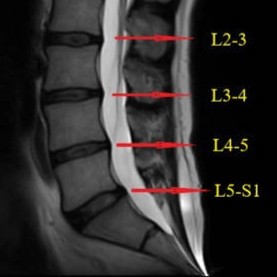

Physiotherapy for L4-L5 Discectomy Recovery